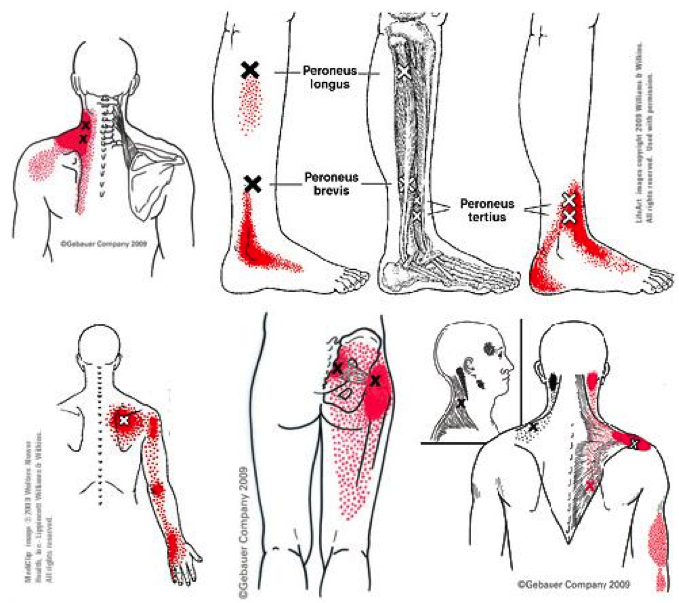

Trigger point Archives • Physical Health Media

Pin by Kevin on Dry Needling (With images) | Trigger points, Massage …